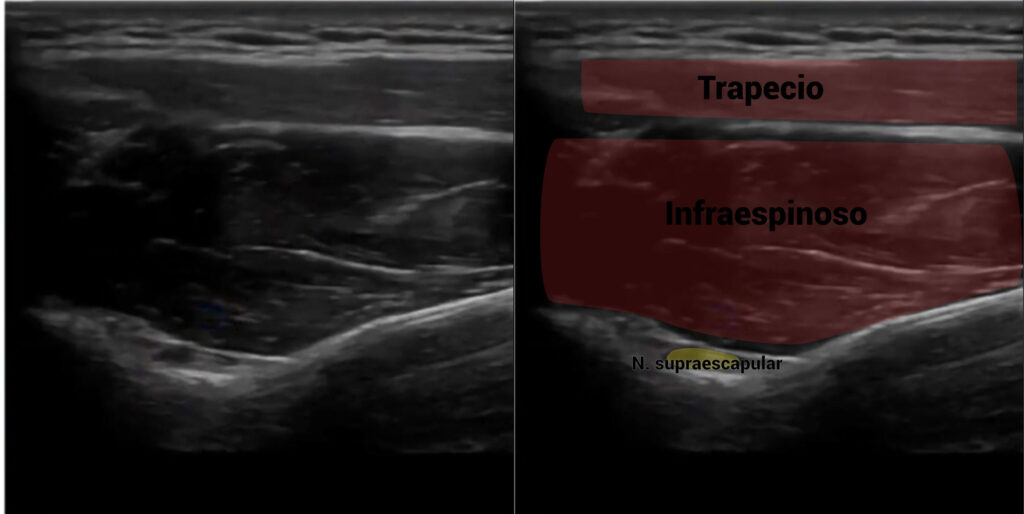

A nivel ecográfico, lo veremos de la siguiente forma:

Nervio axilar o circunflejo

Abordaje invasivo del nervio supraescapular

El abordaje que recomendamos para el nervio supraescapular es en la fosa supraespinosa. Mediante nuestra guía ecográfica, detectaremos una pequeña depresión, correspondiente a la escotadura de la escápula. Es ahí donde se encontrará el nervio supraescapular.

La entrada se hará en eje largo, atravesando con nuestra aguja los vientres musculares del trapecio, supraespinoso, hasta llegar al nervio.